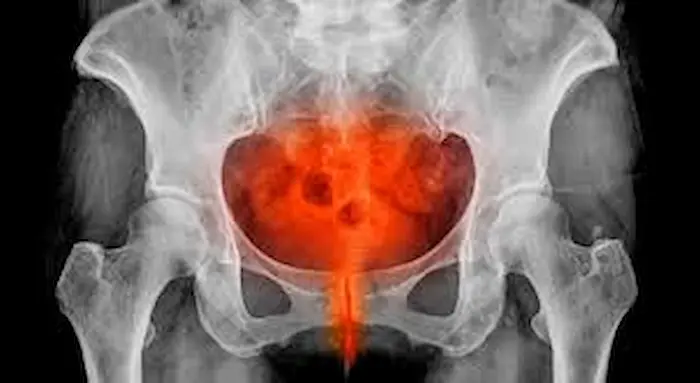

الفحوصات التصويرية

الموجات فوق الصوتية (Ultrasound): تُستخدم للكشف عن التهابات في قناتي فالوب أو وجود خُراجات.

التصوير بالرنين المغناطيسي (MRI): قد يُلجأ إليه في الحالات المعقدة لمزيد من الدقة.